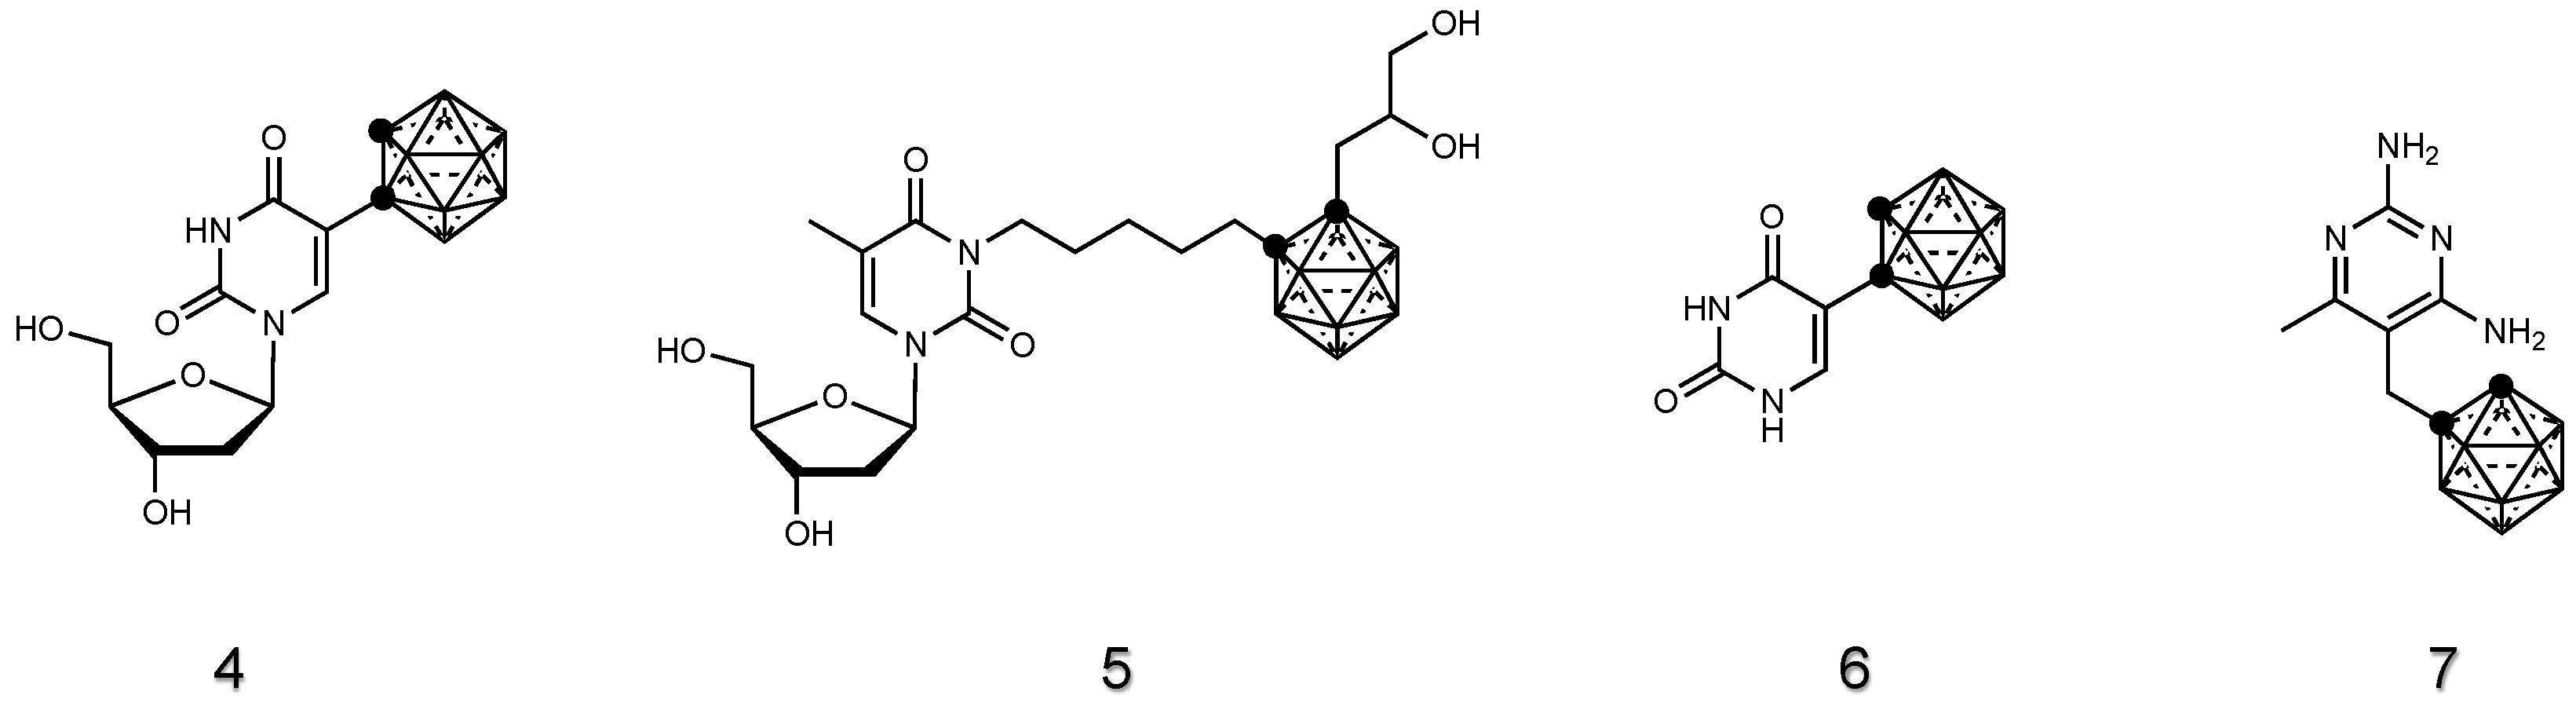

2.1.2. Nucleoside Derivatives of Carboranes

2.1.3. Drug Derivatives of Carboranes